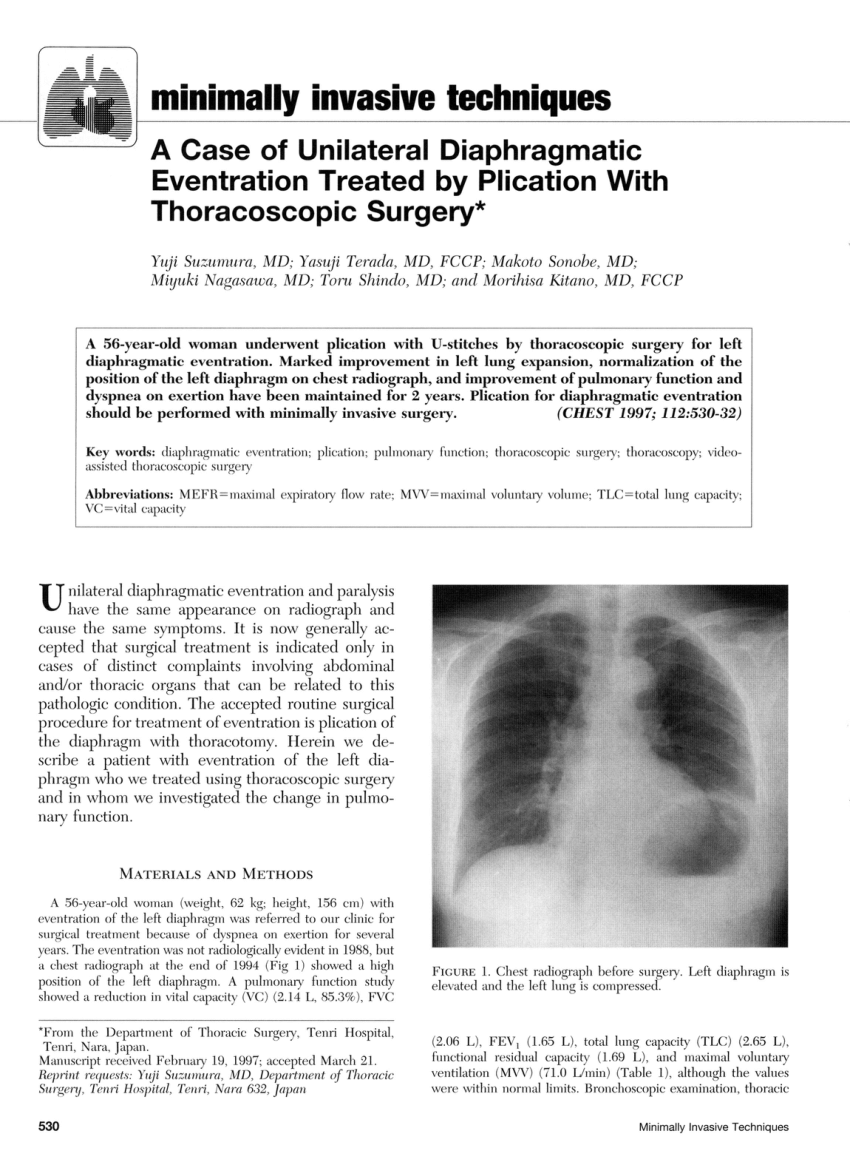

Smoking is the primary cause of emphysema which makes it a preventable illness. Diaphragm weakness due to medical intervention most commonly occurs as a result of physical trauma to the phrenic nerves or diaphragm muscle. Surgical treatment is an option for more advanced cases or if breathing becomes so impacted daily life is affected.

Place one hand on your abdomen and breathe deeply. This procedure is used in patients with unilateral paralysis and occasionally bilateral. These medicines help to decrease or block stomach acid.

You may not need any treatment. Depending on the severity of injury to the diaphragm some doctors recommend non-surgical options to treat the breathing issues associated with diaphragm weakness and paralysis.

The rise in intraabdominal pressure further increases intrathoracic and lung volume by pushing the lower rib cage outward. In severe cases when there is no simple treatment that can relieve dyspnea your doctor may prescribe morphine. Diaphragmatic dysfunction caused by transverse myelitis or leukemic infiltration of the cervical spinal cord in a patient with leukemia and shortness of breath. Diaphragmatic plication a surgical procedure that pulls the diaphragm down by introducing a repeated series of continuous sutures across the diaphragm and pulling the muscle taut. A bedside fan or open window with a breeze are also simple but very effective treatments to lessen dyspnea. Depending on the severity of injury to the diaphragm some doctors recommend non-surgical options to treat the breathing issues associated with diaphragm weakness and paralysis. P E Pulmonary embolism.